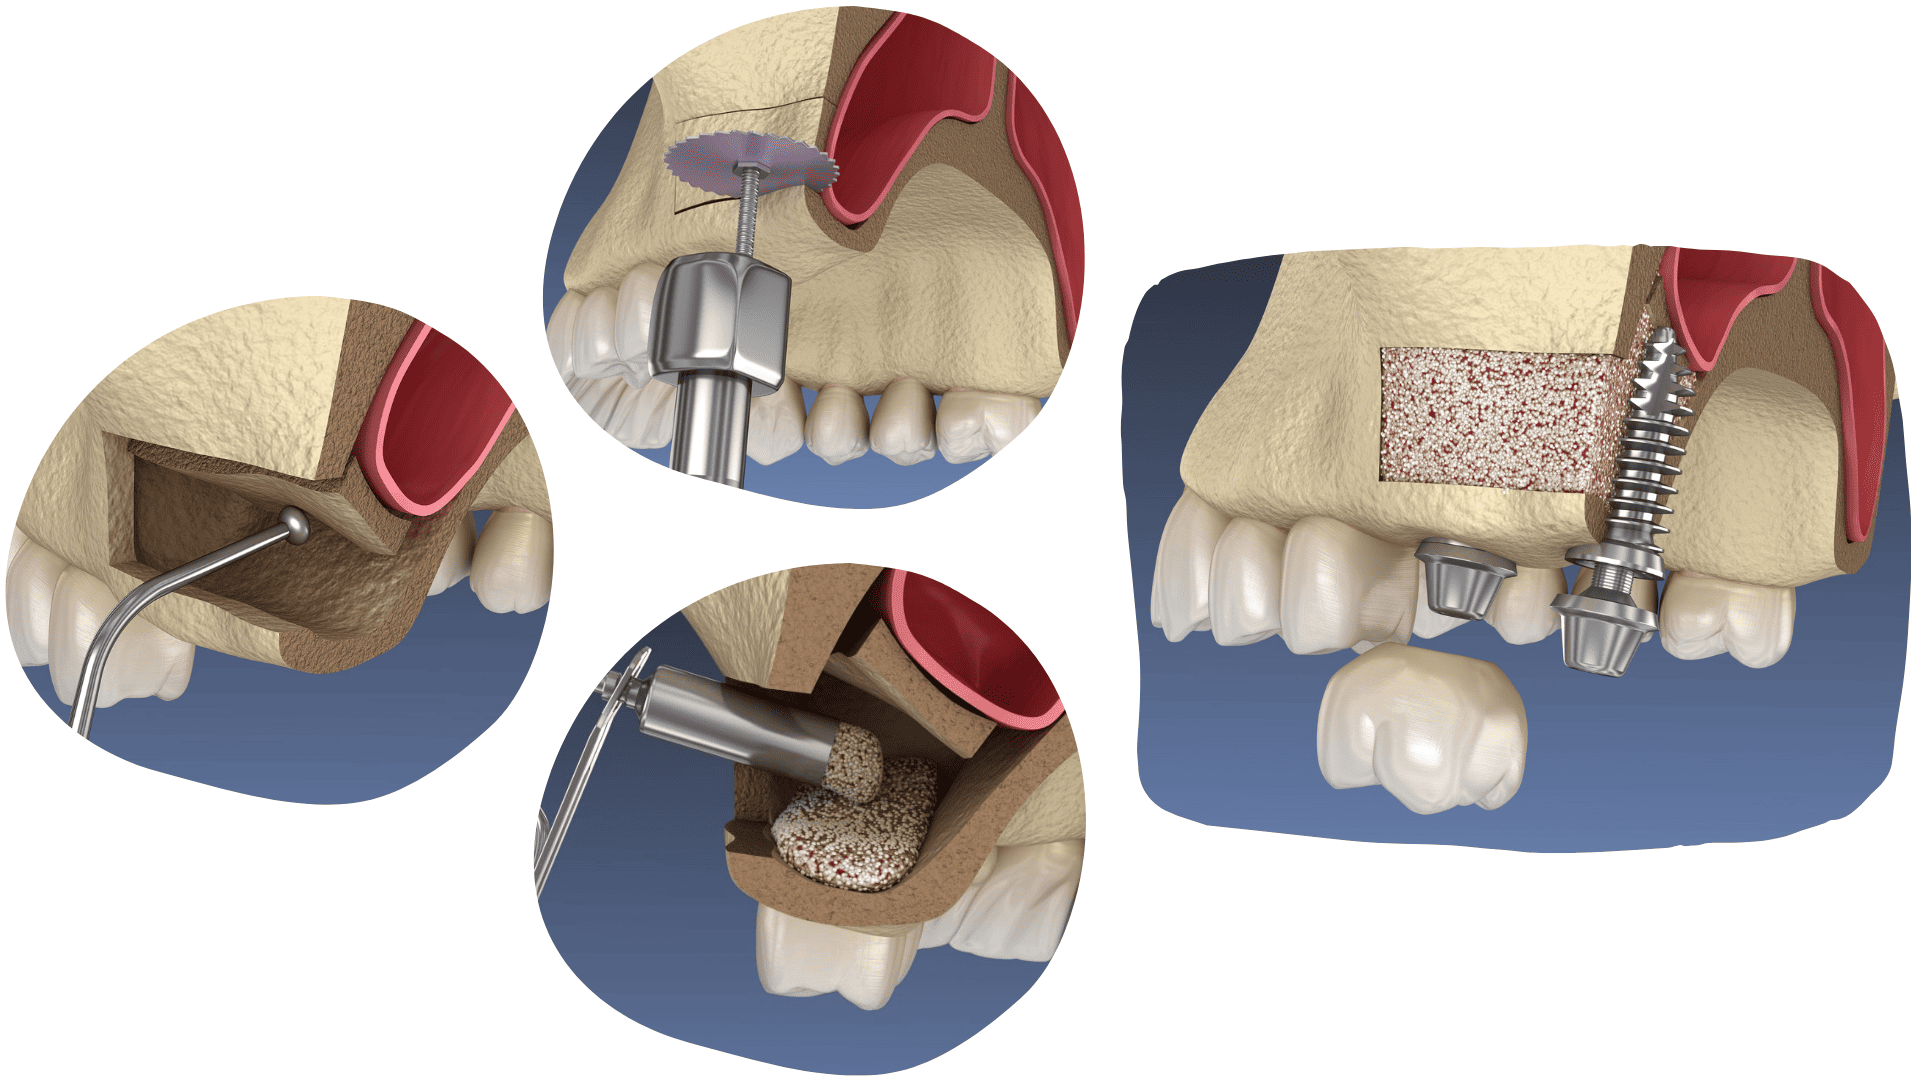

SINUS LIFT

If a lost tooth is not replaced in time, jawbone loss occurs, and the sinuses occupy the space where the bone once was. Because of this, it may not be possible to place an implant immediately, and a sinus lift is required.

A sinus lift is an oral surgical procedure in which the floor of the maxillary sinus is raised and artificial bone is added to create a solid foundation for implant placement.

In cases of minor bone loss, the implant can be placed immediately, simultaneously with the sinus lift, while in cases of greater loss, it is necessary to wait for the new bone to integrate and strengthen.

The procedure is painless and performed under local anaesthesia.